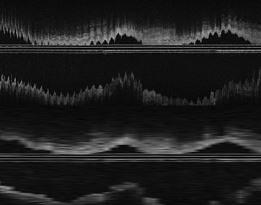

Aims: Images acquired of coronary vessels during a pullback of time-domain optical coherence tomography (OCT) are influenced by the dynamics of the heart. This study explores the feasibility of applying an in-house developed retrospective image-based gating method for OCT and the influence of catheter dislocation and luminal changes during the cardiac cycle on the outcome of quantitative OCT (QOCT). Methods and results: The gating method was developed using Matlab (The Mathworks, Natick, MA, USA) and operates in a fully-automatic manner. OCT image data of 20 randomly selected patients, acquired with a commercially available system (Lightlab Imaging, Westford, MA, USA), were pulled from our OCT database for development and validation. Twelve of the 20 datasets could be gated; the other eight pullbacks could not be gated due to a lack of motion induced artefacts. Computations required approximately 30 minutes/dataset. Quantitative comparisons between the gated and the non-gated QOCT results showed significant differences for mean areas and volumes (p < 0.001) and mean relative differences of -11% (range -2 up to -20%) for lumen areas (gated) and –13% (range –5 up to –24%) for volumes. Conclusions: Retrospective image-based time-domain OCT gating in the presence of motion induced artefacts is feasible. Significant changes in coronary lumen dimensions during the cardiac cycle were observed by OCT and in consequence, quantitative gated OCT analysis showed significant differences compared to non-gated QOCT analyses.